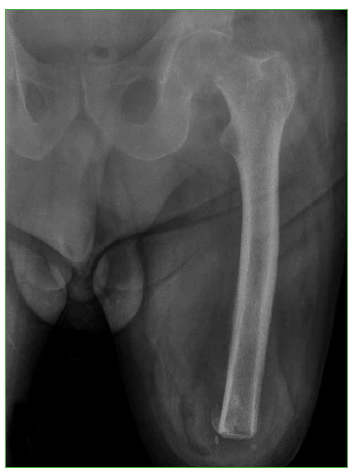

Las fracturas de cadera en pacientes con amputación del miembro homolateral son lesiones infrecuentes que representan un reto para el cirujano ortopédico. Presentamos el caso de un hombre de 63 años con amputación supracondílea izquierda, que sufre una fractura de cuello femoral izquierdo por caída de su propia altura. La colocación apropiada del implante es esencial para obtener buenos resultados clínicos posoperatorios. Para la exposición y la colocación del implante se utilizó un clavo de Steinmann en el trocánter mayor. No se observaron complicaciones clínicas ni radiográficas en un seguimiento de 15 meses. Creemos que el empleo del clavo de Steinmann colocado en una correcta posición es una buena alternativa por considerar para poder controlar el miembro al realizar una artroplastia y así disminuir los riesgos de colocar la prótesis en mala posición y el tiempo quirúrgico.Descargas